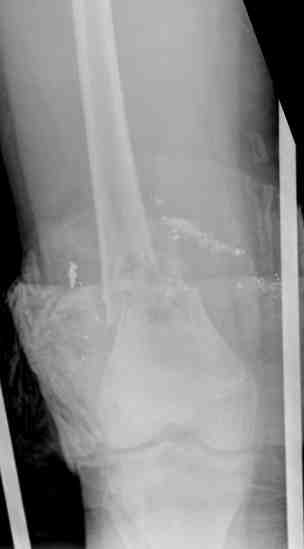

Выше представлены рентгенограммы открытого оскольчатого перелома нижней трети голени X-rays of Compound Comminuted # Distal/3 Lt Tibia

Операционные снимки перед и после наложения аппарата Илизарова In operation room before and after Ilizarov apparatus has been applied

Послеоперационные рентгенограммы Postoperative X-rays

В нижнем ряду представлены рентгенограммы после окончательной репозиции. And final reduction after Hexapod program has been finished